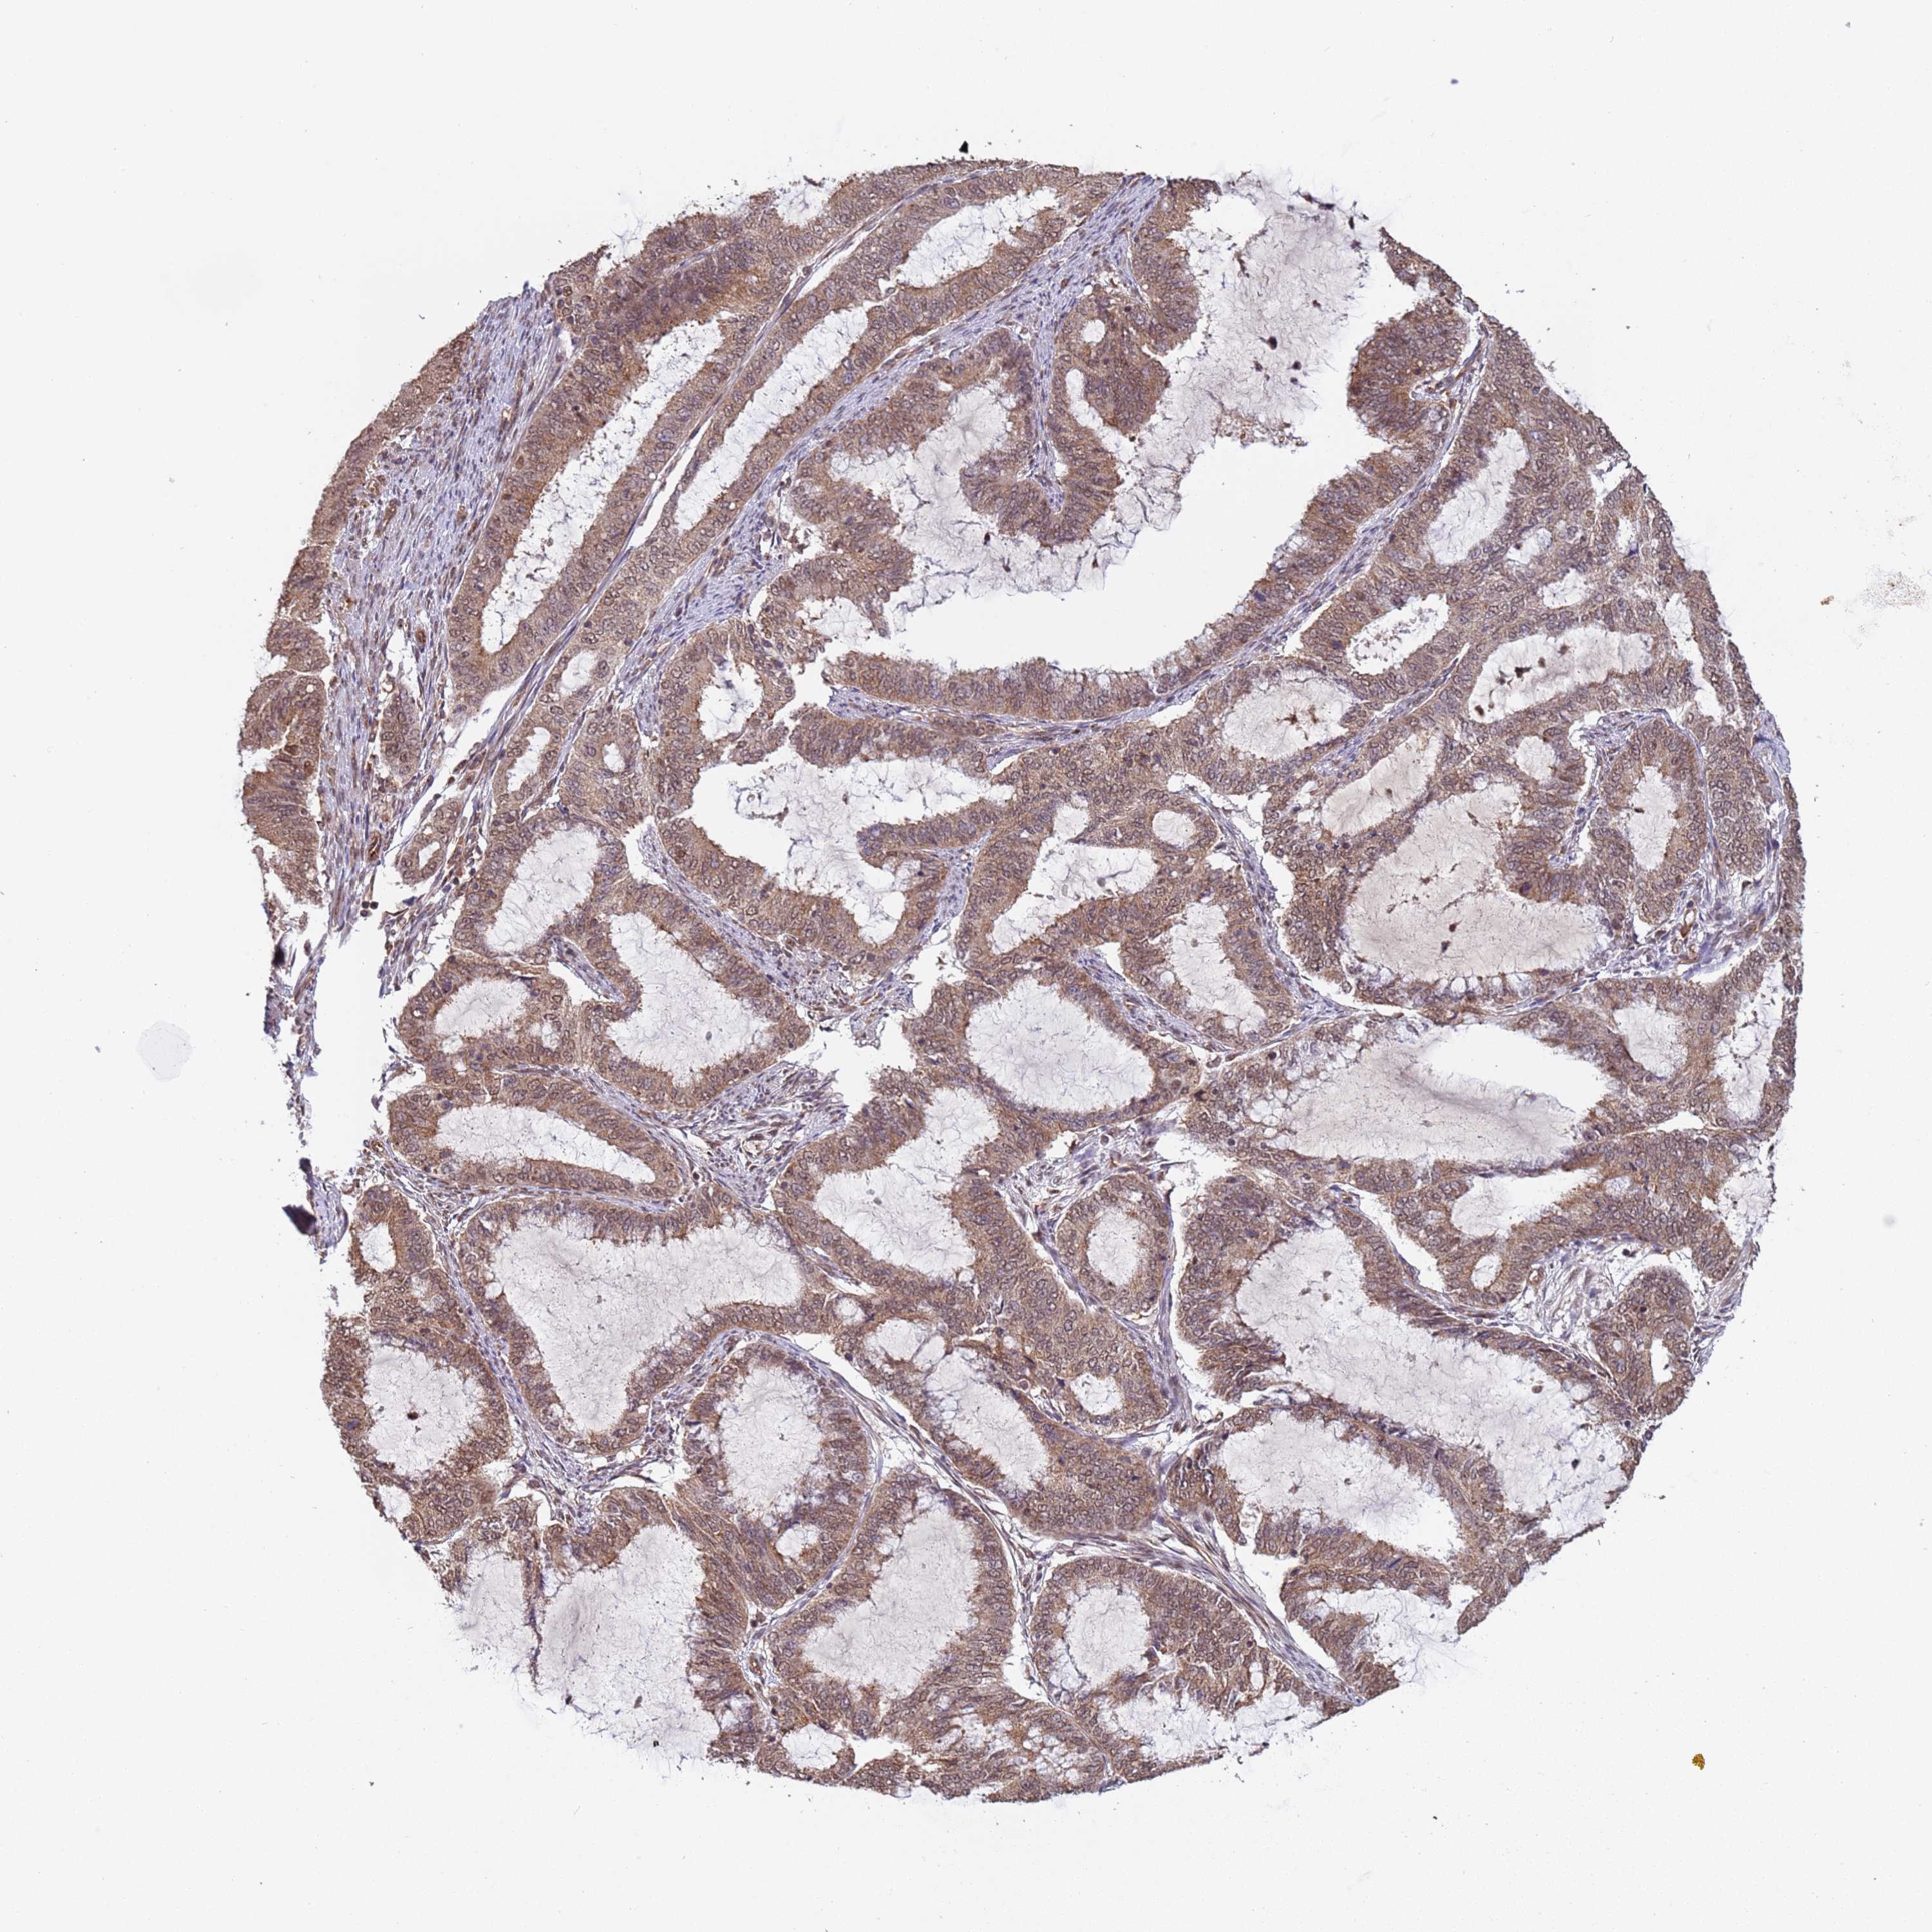

ENDOMETRIAL CANCER - Protein expressioni

A mouse-over function shows sample information and annotation data. Click on an image to view it in a full screen mode. Samples can be filtered based on level of antibody staining by selecting one or several of the following categories: high, medium, low and not detected. The assay and annotation is described here.

Note that samples used for immunohistochemistry by the Human Protein Atlas do not correspond to samples in the TCGA dataset.

Antibody stainingi

Antibody staining in the annotated cell types in the current human tissue is reported as not detected, low, medium, or high, based on conventional immunohistochemistry profiling in selected tissues. This score is based on the combination of the staining intensity and fraction of stained cells.

Each image is clickable and will lead to virtual microscopy that enables deeper exploration of all samples and also displays staining intensity scores, fraction scores and subcellular localization as well as patient and tissue information for each sample.

Antibody HPA045624

Staining

High

Medium

Low

Not detected

Intensity

Strong

Moderate

Weak

Negative

Quantity

>75%

75%-25%

<25%

None

Location

Nuclear

Cytoplasmic/membranous

Cytoplasmic/membranous,nuclear

Adenocarcinoma, NOS